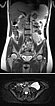

Koronare (oben) und axiale (unten) T2-gewichtete Haste-Sequenzen ohne Kontrastmittel in der 21. Schwangerschaftswoche.

Während der Schwangerschaft deutliche Größenzunahme der VM, die ventral des linken Musculus posas als signalintense Läsion zur Darstellung kommt, ohne Verdrängung oder Kompression der Plazenta.

Koronare native T2-Haste-Sequenzen zur Verlaufsbeurteilung der VM ventral auf dem linken Musculus psoas aufsitzend in der 21. Schwangerschaftswoche. Während der Gravidität entwickelt die Patientin auch eine Harnstauungsniere Grad III rechts.

In der axialen T2-HASTE-Sequenz in der 21. Schwangerschaftswoche grenzt die VM an die Plazenta, ohne Verdrängung oder Verlagerung von Uterus oder des Fötus.